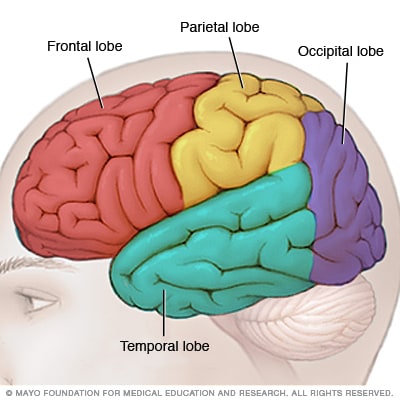

The brain is made up of 3 main parts: the cerebrum, the cerebellum, and the brain stem. The meninges, which surround the brain, are also considered part of the brain.

The cerebrum. This is the largest part of the brain. It contains 2 cerebral hemispheres on either side of the brain that each control the opposite side of the body. It is divided into 4 lobes where specific functions occur:

The frontal lobe controls reasoning, emotions, problem-solving, expressive speech, and movement.

The parietal lobe controls the sensations of touch, such as pressure, pain, and temperature. It also controls parts of speech, visual-spatial orientation, and calculation.

The temporal lobe controls memory, special senses such as hearing, and the ability to understand spoken or written words.

The occipital lobe controls vision.

The cerebellum. The cerebellum is located at the back part of the brain below the cerebrum. It is responsible for coordination and balance, and it controls functions on the same side of the body.

Brain lobes

Each side of your brain contains four lobes. The frontal lobe is important for cognitive functions and control of voluntary movement or activity. The parietal lobe processes information about temperature, taste, touch and movement, while the occipital lobe is primarily responsible for vision. The temporal lobe processes memories, integrating them with sensations of taste, sound, sight and touch.

The main part of the brain is called the cerebrum. Brain tumors in different parts of the cerebrum might cause different symptoms.

- Brain tumors in the front of the brain. The frontal lobes are in the front of the brain. They control thinking and movement. Frontal lobe brain tumors might cause balance problems and trouble walking. There might be personality changes, such as forgetfulness and lack of interest in usual activities. Sometimes family members notice that the person with the brain tumor seems different.

- Brain tumors in the middle of the brain. The parietal lobes are in the upper middle part of the brain. They help process information about touch, taste, smell, vision and hearing. Parietal lobe brain tumors can cause problems related to the senses. Examples include vision problems and hearing problems.

- Brain tumors in the back of the brain. The occipital lobes are in the back of the brain. They control vision. Occipital lobe brain tumors can cause vision loss.

- Brain tumors in the lower part of the brain. The temporal lobes are on the sides of the brain. They process memories and senses. Temporal lobe brain tumors can cause memory problems. They might cause someone to see, taste or smell something that isn't there. Sometimes the taste or smell is unpleasant or unusual.